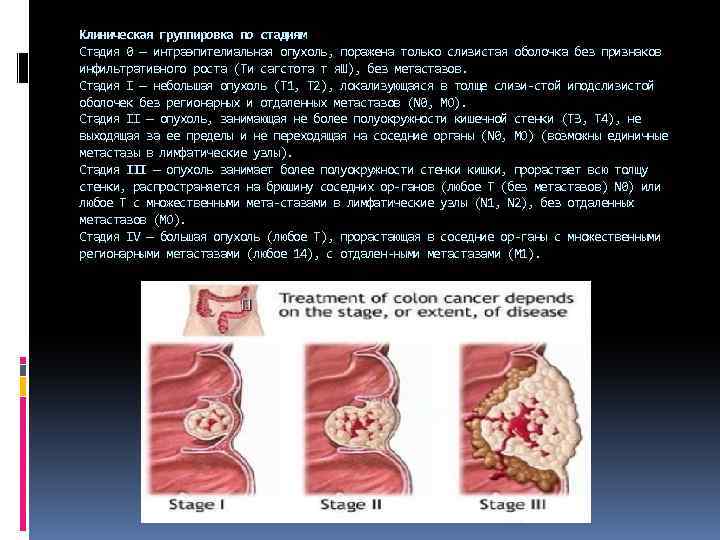

Клиническая группировка по стадиям Стадия 0 — интраэпителиальная опухоль, поражена только слизистая оболочка без признаков инфильтративного роста (Ти сагстота т я. Ш), без метастазов. Стадия I — небольшая опухоль (Т 1, Т 2), локализующаяся в толще слизи стой иподслизистой оболочек без регионарных и отдаленных метастазов (N 0, МО). Стадия II — опухоль, занимающая не более полуокружности кишечной стенки (ТЗ, Т 4), не выходящая за ее пределы и не переходящая на соседние органы (N 0, МО) (возможны единичные метастазы в лимфатические узлы). Стадия III — опухоль занимает более полуокружности стенки кишки, прорастает всю толщу стенки, распространяется на брюшину соседних ор ганов (любое Т (без метастазов) N 0) или любое Т с множественными мета стазами в лимфатические узлы (N 1, N 2), без отдаленных метастазов (МО). Стадия IV — большая опухоль (любое Т), прорастающая в соседние ор ганы с множественными регионарными метастазами (любое 14), с отдален ными метастазами (М 1).